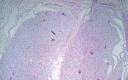

Plexiform neurofibromas are benign tumors originating from peripheral nerve sheaths, generally associated with Neurofibromatosis Type 1 (NF1). They are diffuse, painful and sometimes locally invasive, generating cosmetic problems. This report discusses an adolescent patient who presented with an isolated, giant plexiform neurofibroma on her leg that was confused with a vascular lesion due to its clinical aspects. Once the diagnosis was confirmed by surgical biopsy, excision of the lesion was performed with improvement of the symptoms.